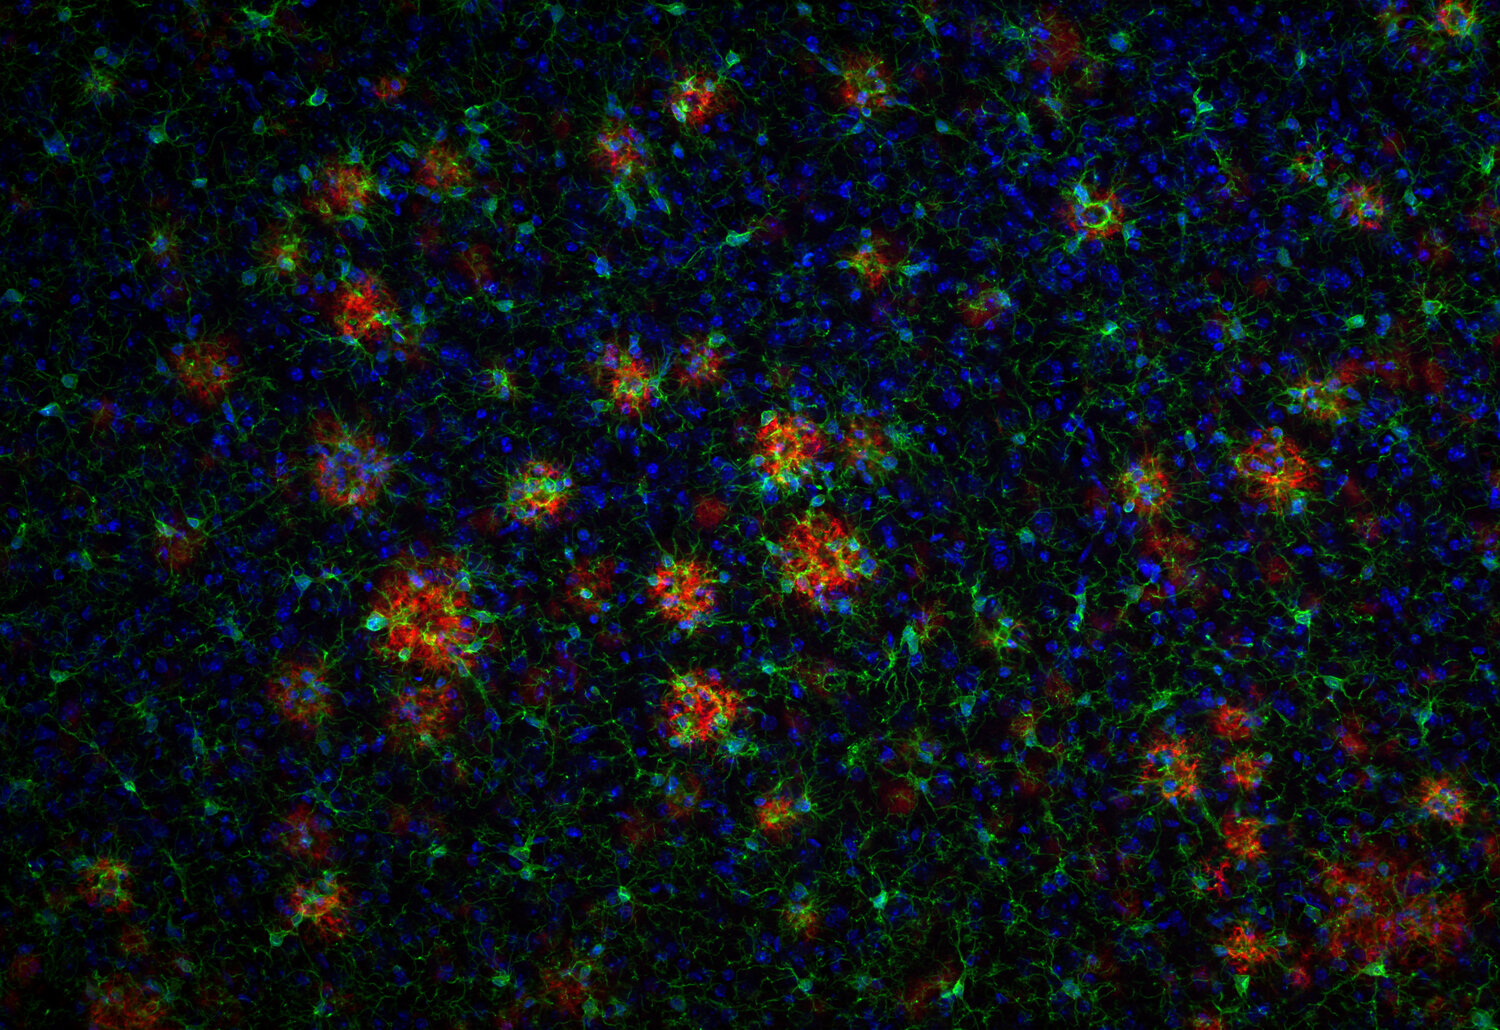

Abeta peptides are major components of neuritic plaques in Alzheimer's disease

IHC: 1 : 500 gallery

IHC-P: 1 : 100 up to 1 : 500 gallery

IHC: Antigen retrieval with formic acid is required.

IHC-P: Antigen retrieval with citrate buffer pH 6, followed by formic acid treatment, is required.

Transplantation of bone marrow derived macrophages reduces markers of neuropathology in an APP/PS1 mouse model.

Costa-Marques L, Arnold K, Pardon MC, Leovsky C, Swarbrick S, Fabian C, Stolzing A

Translational neurodegeneration (2019) 8: 33. 218 011BT IHC; tested species: mouse

Amyloid deposits, also called plaques, of Alzheimer's patients consist of several protein components like the amyloid beta-peptides (Abeta, ) 1-40/42 and additional C- and N-terminally truncated and modified fragments. Very abundant are the isoaspartate (isoAsp)-Abeta and pyroglutamyl (pGlu)-Abeta peptides. The latter are formed by cyclization of the N-terminal glutamate at position 3 or 11 catalyzed by glutaminyl cyclase (QC) resulting in very amyloidogenic and neurotxic variants of Abeta; Abeta-pE3 and Abeta pE11.

In contrast to extracellular plaques that do not perfectly correlate with Alzheimer´s disease intraneuronal Abeta accumulation and vascular Abeta deposits have gained more and more evidence to be among the crucial factors responsible for progressive neuron loss.